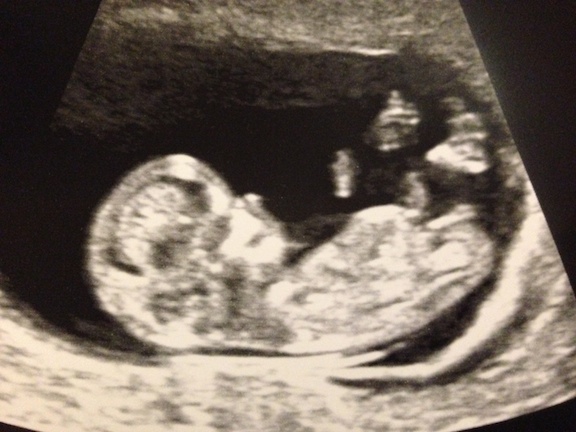

I know it's early, and still 50/50 at this point but I'm getting my panorama results next week so I'll know then :). I'd love to get some guesses for fun. Doesn't look like my DS nub so I've got my fingers crossed!

Too early to guess but it does look stacked so if I had to guess it would be blue - very early though. Good Luck :) update us won't you?

It is at a girl angle currently but the slight stacking looks like a boy nub that has yet to rise. I hesitate to guess due to gestation. 50/50 from me. The photos are lovely & clear though. What a cutie! 😊

I definitely agree with everyone. I've seen a lot of boy nubs that look the same in the 11th week. I'll just keep my fingers crossed it stays girly! My boys was sticking straight up so there was no question.

It's a boy!!